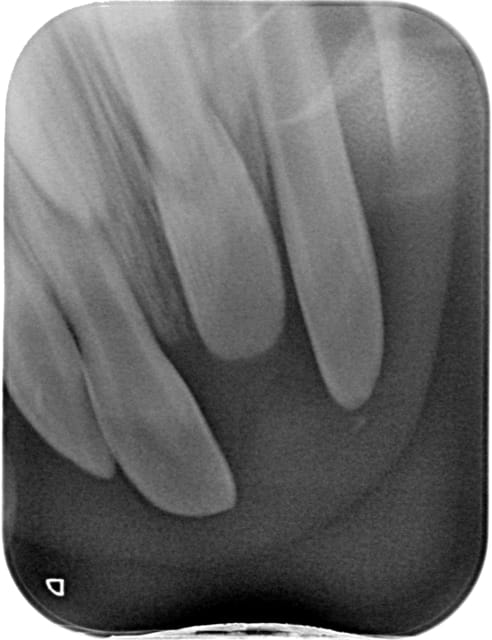

mi-janvier chute avec intrusion complète de la dent ( je l'ai vu à J+5 ), on voyait à peine le bord libre,

revue la semaine dernière, la face vestibulaire de la dent est

visible au fond du vestibule mais la dent n'a pas bougée

à la radio la racine semble plus courte donc pour moi elle est passée complétement en vestibulaire du germe,